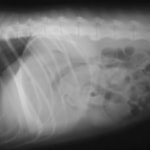

術後レントゲン

腹部臓器が腹腔内に戻り、腹部と胸部の境界および心臓や肺の陰影が明瞭に見えるようになりました。